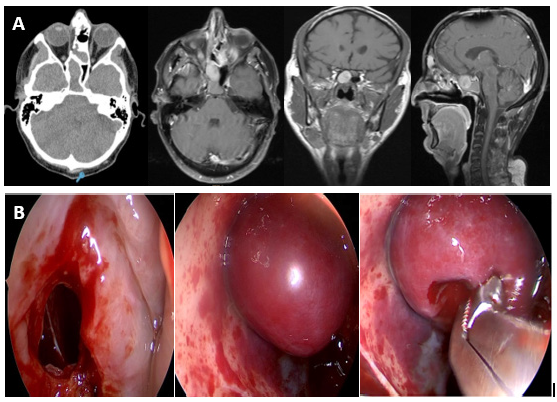

A 49-year-old man with a history of combined endoscopy-assisted cranionasal approach and postoperative chemoradiotherapy seven years earlier, for an esthesioneuroblastoma that involved ethmoids and had an endocranial extension. During routine checks, and for referring intermittent headache, imaging studies were requested. Computed tomography and nuclear magnetic resonance with contrast showed two lesions of different density compatible with sphenoid mucocele. Through an endonasal approach with endoscopes and intraoperative navigation, a wide sphenoidotomy was performed and the mucocele was marsupialized, aspirating mucous secretions. A red and round, non-pulsatile tumor was observed behind, in contact with the roof and the left wall of the sphenoid sinus. The tumor was resected with cutting forceps. He was discharged 24 hours after the surgery. The deferred pathological study reported “Hematic material with fibrin, some lymphocytes and leukocytes” compatible with sphenoid organized hematoma. The patient had no more headache and in the endoscopic controls for 2 years the sphenoidal sinus was ventilated and without recurrence of the hematoma (Figure 2).

Figure 2:A: Organized hematoma of the sphenoid sinus-tomography and magnetic resonance with contrast. B: Transnasal sphenoidotomy and resection of an organized hematoma.